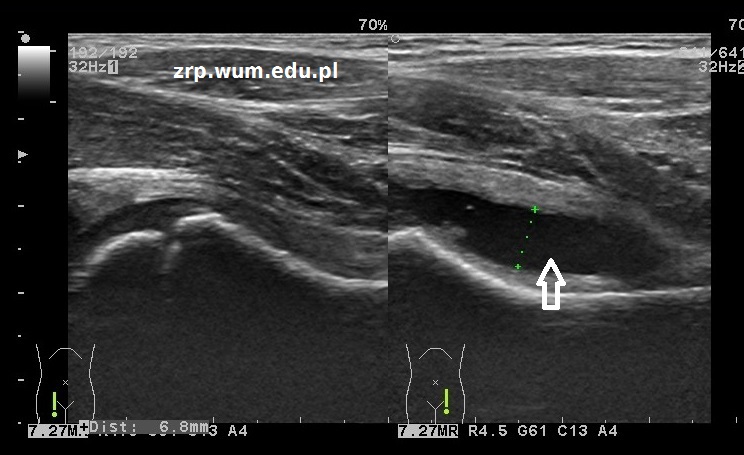

Rozpoznanie: W badaniu USG stawów biodrowych - w lewym stawie biodrowym zwiększona ilość płynu (strzałki), warstwa do 7mm. Głowa kości udowej prawidłowa. Obraz zwiewnego zapalenia stawu biodrowego (coxitis fugax). W prawym stawie biodrowym - obraz usg w normie.